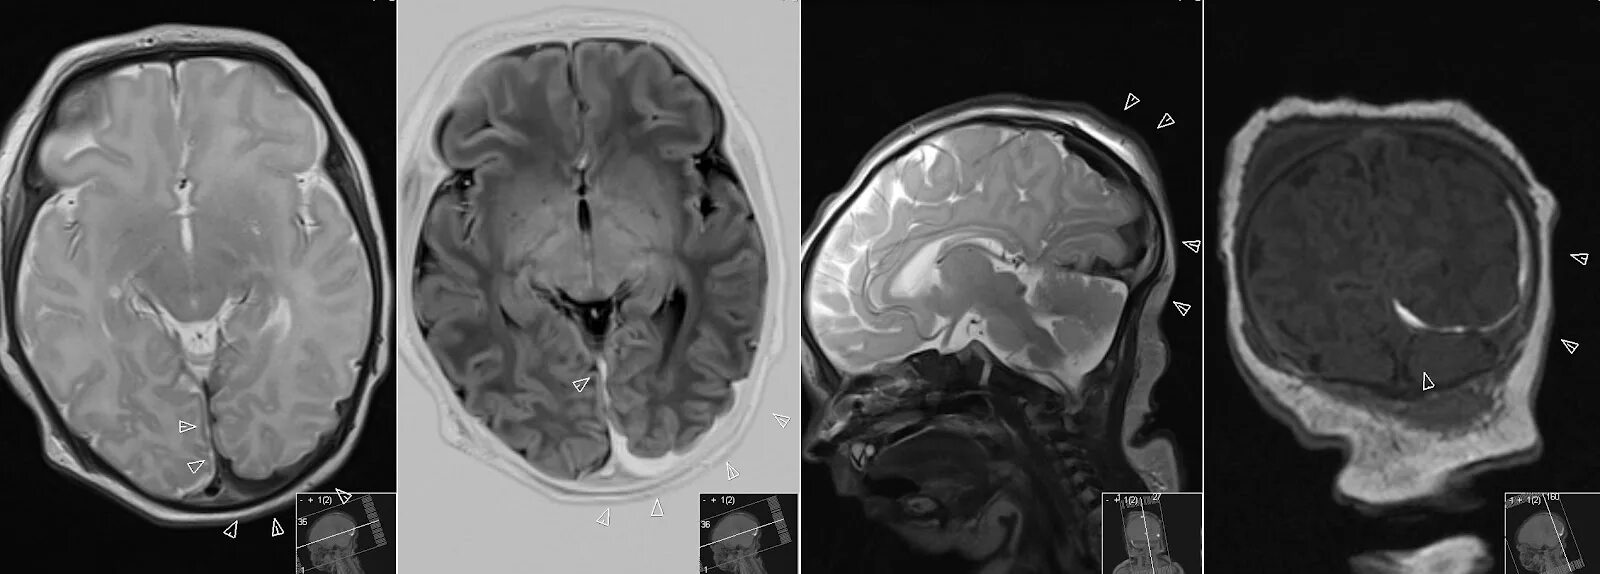

Субарахноидальное пространство зрительных нервов